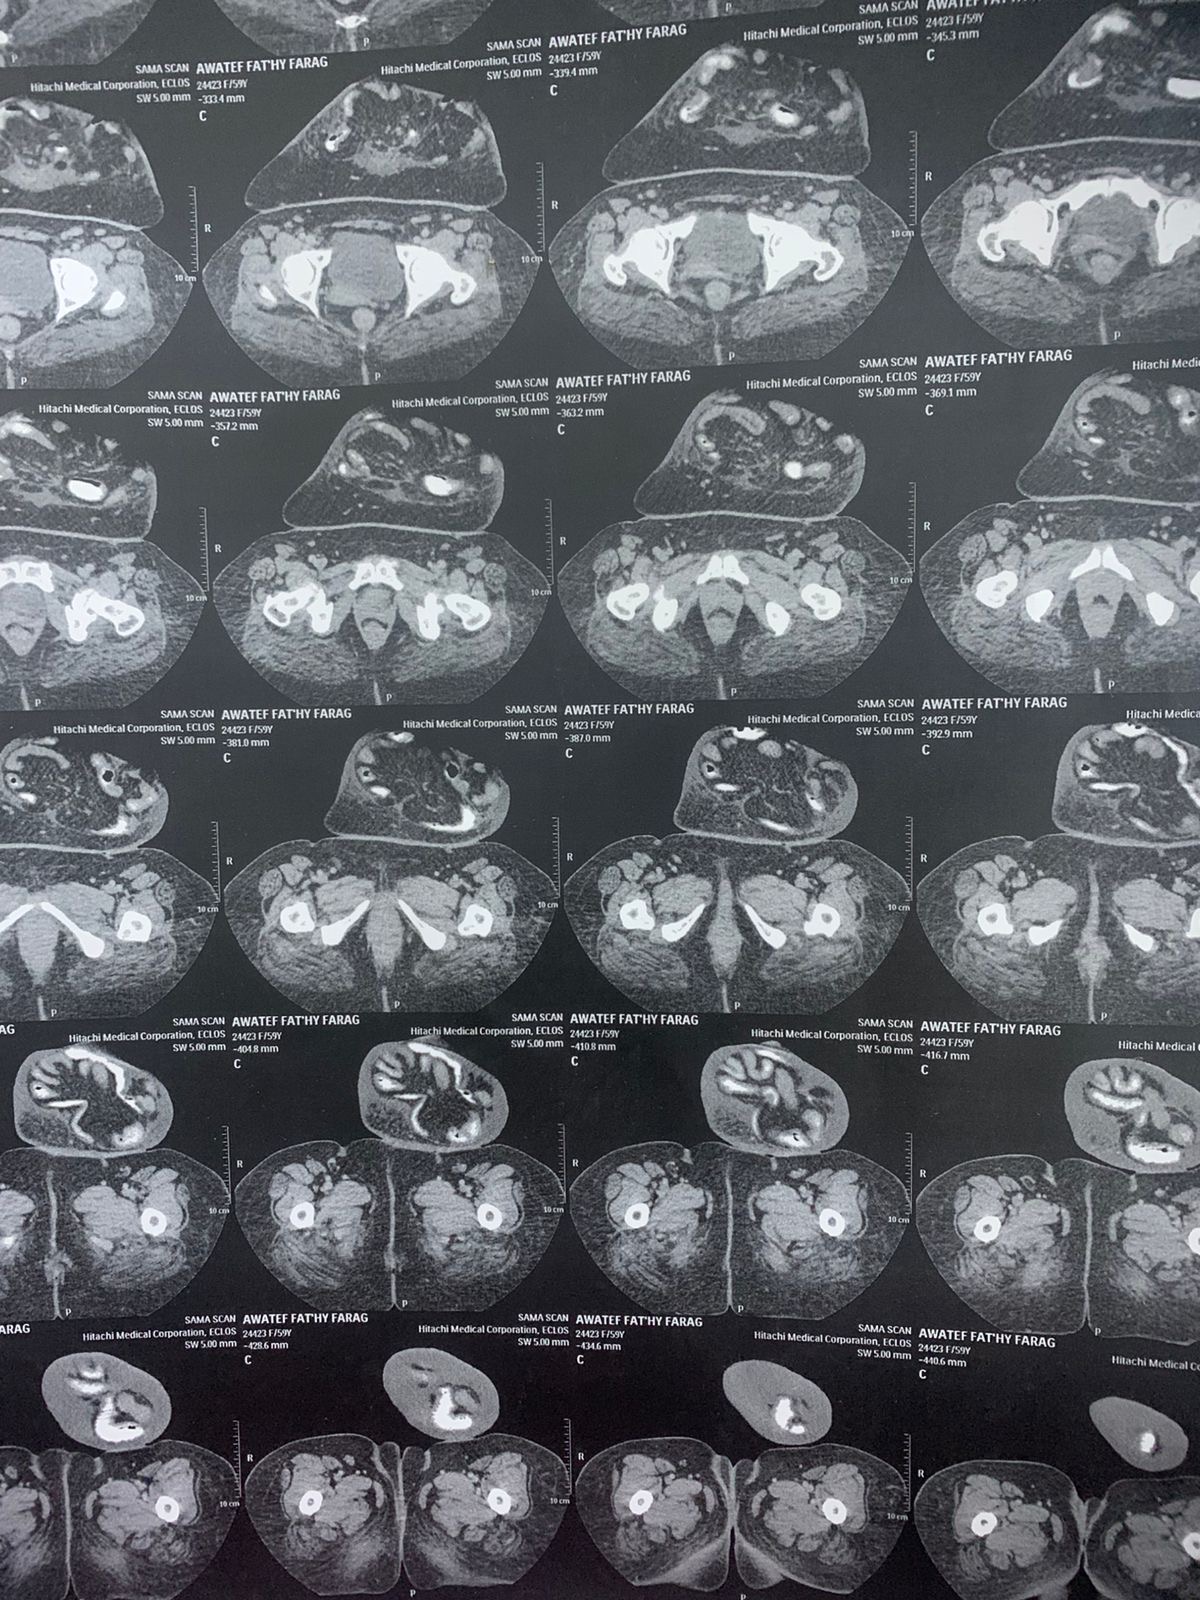

والدتي عندها ٦٠ سنه هي مريضة فتاق سري قديم وضخم ومسبب لها تعب ومغص هي مريضه سكر نوع ثاني والحاله الصحيه ممتازه الحمدلله بس هي بتخاف شويه هل يمكن اجراء عملية الفتاق السري ولا في خطورة علي حياتها

الملفات المرفقة: